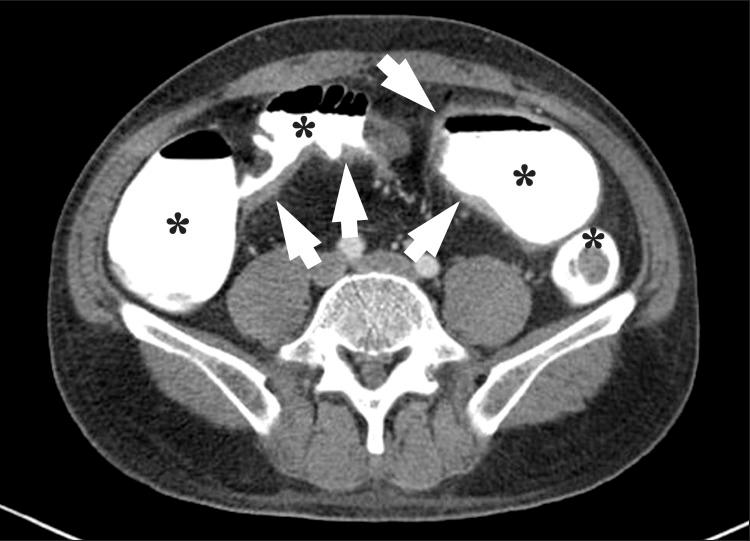

Imaging of the small bowel is complicated by its length and its overlapping loops. Recently, however, the development of crosssectional imaging techniques, such as computed tomography enterography (CTE) and magnetic resonance enterography (MRE) has shifted fundamental paradigms in the diagnosis and management of patients with suspected or known Crohn's disease (CD). CTE and MRE are noninvasive imaging tests that involve the use of intraluminal oral and intravenous contrast agents to evaluate the small bowel. Here, we review recent advances in each cross-sectional imaging modality, their advantages and disadvantages, and their diagnostic performances in the evaluation of small bowel lesions in CD.